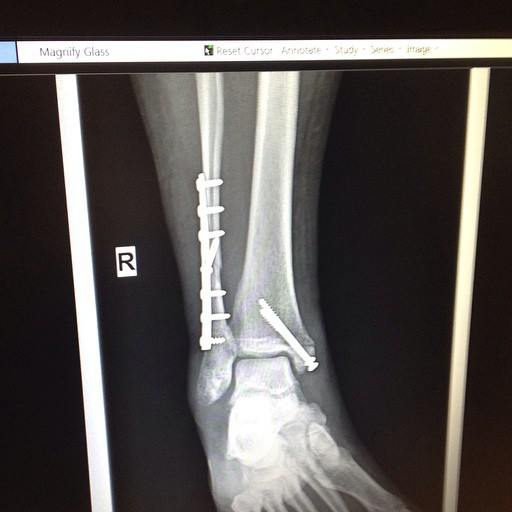

I’ve been back skating now for as long as I’d been out and I can honestly say I feel more confident, more sure of myself, and better than I was before my ankle break. Big Injury doesn’t have to be the end. There are plenty of people in my life who think I’m crazy for going back to a sport that landed me in an operating room with a bunch of metal in my leg, and the possibility of more to come. I am still scared sometimes. I think “what if…” each time I lace up my skates and head out onto the track. But that’s the thing about derby; once you fall in love with it, you never want to leave it. It’s a part of who you are. I even got myself a little reminder shortly after I started skating again, a tattoo of a robot derby girl on the inside of of my ankle between the scars of where my new metal pieces now reside (her name is Rhonda Swantron and I love her).